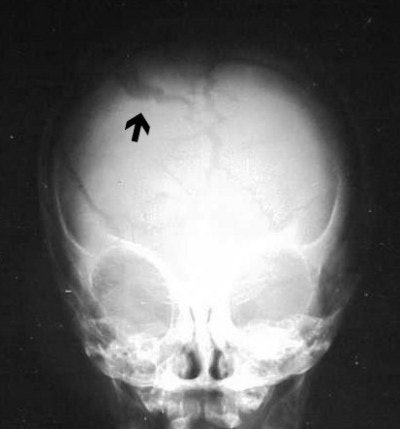

In some cases of non-accidental trauma (formerly called child abuse) we see infants with skull fractures. These eggshell fractures (figures 9 and 10) are consistent with the child’s being held by his ankles and swung against an inanimate object, in this case, a coffee table.

![]() |

| Figure 9 |

| Figure 10 |